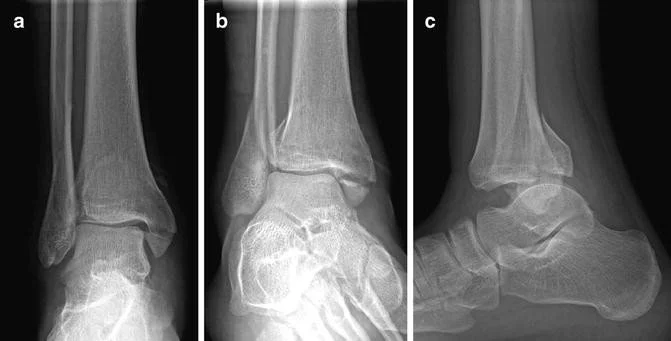

An ankle fracture is a break in one or more of the bones that form the ankle joint, most commonly the tibia (shinbone), fibula (outer leg bone), and occasionally the talus, which connects the leg to the foot. Ankle fractures are common lower extremity injuries and may occur after a twisting injury, fall, sports-related trauma, or high-energy accidents such as motor vehicle collisions.

Ankle fractures are classified based on which bones are involved and whether the ankle joint remains stable. Common types include:

Isolated fibula fractures

Medial malleolus fractures

Bimalleolar fractures (involving two bones)

Trimalleolar fractures (involving three bones)

More complex fractures may be associated with ligament injury, joint displacement, or instability, which often requires surgical treatment to restore proper alignment.

Diagnosis begins with a thorough history and physical examination, followed by X-ray imaging to evaluate fracture location, alignment, and joint involvement. In certain cases, CT scans may be used to better assess complex fractures and assist with surgical planning.